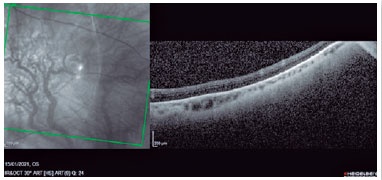

Um ano após o término da quimioterapia, iniciou com recidiva de massa pulmonar hipercaptante no lobo médio. Apresentou cefaleia holocraniana e turvação visual, associado a fotopsias. A tomografia de crânio não evidenciou alterações, mas o mapeamento retiniano demonstrou uma lesão sub-retiniana macular de aspecto esbranquiçado, elevado com cerca de 10 diâmetros papilares, temporal superior. Acuidade visual olho direito de 20/20, sem lesões dignas de nota; e 20/50 no olho esquerdo, associada à lesão sólida, endofítica, com delimitação irregular, hipocrômica, temporal superior, medindo na base cerca de 10 mm à retinografia e altura de 2,8 mm ao ultrassom, com presença de descolamento seroso setorial inferior da retina e ausência de ângulo Kappa. À tomografia de coerência óptica (OCT) observou-se descolamento da retina neurossensorial, com acometimento perifoveal e abaulamento coroidal temporal superior, com compressão da retina externa (Figura 1).

Figura 1. Tomografia de coerência óptica (TCO) no A-scan (à esquerda) uma massa de refletividade heterogenia com margens irregulares e demonstrando no B-scan (à direita) uma elevação com bordas irregular em topografia de coroide com fluido sub-retiniano adjacente na arcada temporal superior, podemos observar uma desorganização das camadas externas com pontos hiperreflectivos.